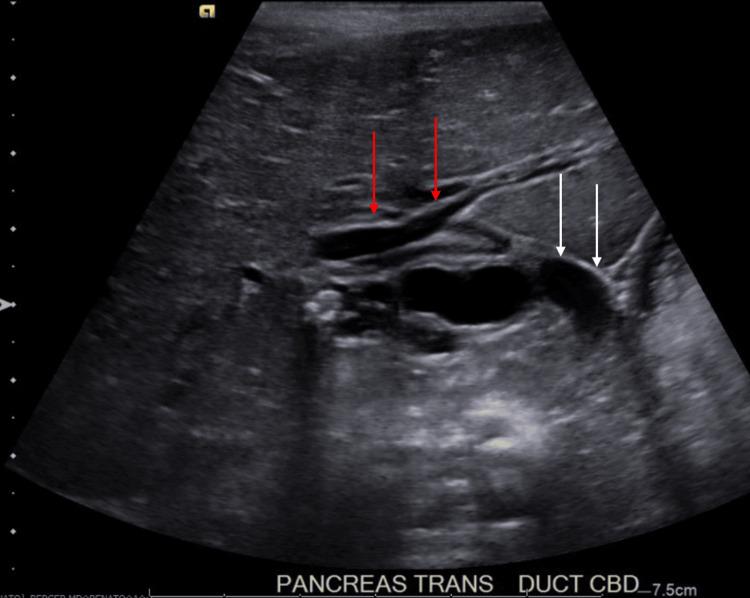

Cholelithiasis, or gallstone(s), is a leading cause of healthcare utilization in the United States. It is more common in adults but can occur in the pediatric population as well. The following is a case report of choledocholithiasis in a 19-month-old girl. A 19-month-old girl with abdominal pain presented to the emergency department (ED) after being found to have cholelithiasis on an outpatient abdominal ultrasound (US). Three days prior to presentation, the patient was seen by her pediatrician for fussiness, decreased oral intake, and non-bloody, non-bilious emesis. She was diagnosed with a suspected urinary tract infection (UTI) and prescribed amoxicillin-clavulanate for empiric treatment. The following day, the patient returned to her pediatrician for worsening abdominal pain; she was given one dose of intramuscular ceftriaxone and scheduled for outpatient abdominal US. Her past medical history is significant for omphalocele status post-surgical correction, several congenital cardiac defects, bilateral small kidneys, and poor weight gain. The patient has a normal chromosomal microarray and no family history of hepatobiliary/pancreatic disease. In the ED, the patient was afebrile and hemodynamically stable. Physical examination was significant for mild hepatomegaly, mild abdominal tenderness without peritoneal signs, and the presence of a well-healed surgical scar on the abdomen with an underlying abdominal hernia. Laboratory tests were significant for leukocytosis of 14.5×10/microliter (mcL), elevated gamma-glutamyl transferase (GGT) of 305 unit/L (U/L), aspartate aminotransferase (AST) of 86 U/L, alanine aminotransferase (ALT) of 343 U/L, total bilirubin of 2.3 milligram/deciliter (mg/dL), direct bilirubin of 1.6 mg/dL, and lipase of 1,726 U/L. Abdominal US revealed several gallstones and mild to moderate intra- and extrahepatic biliary ductal dilatation likely due to a stone in the distal common bile duct (CBD). Pediatric surgery and gastroenterology recommended admission for pain management and magnetic resonance cholangiopancreatography (MRCP). After admission, the patient was started on ursodiol and piperacillin/tazobactam. MRCP showed a common hepatic duct measuring 13 mm and a 9×5 mm stone in the distal common bile duct. Due to a lack of available outside facilities with the capability to perform endoscopic retrograde cholangiopancreatography (ERCP) in a pediatric patient, medical management was pursued. Throughout her admission, the patient improved clinically, laboratory studies became normal, and pain was controlled. Repeat US showed persistent biliary dilation with cholelithiasis. The patient was cleared for discharge on ursodiol and amoxicillin-clavulanate and close follow-up with pediatrician, pediatric surgeon, and pediatric gastroenterologist. Follow-up US performed two weeks after discharge showed interval resolution of intra- and extrahepatic biliary duct dilatation and cholelithiasis without evidence of cholecystitis. Abdominal pain accounts for 5%-10% of all pediatric ED visits, and although cholelithiasis and choledocholithiasis are rare in the pediatric population, as this case demonstrates, it is an important differential diagnosis. Observation is the recommended management for asymptomatic patients as most cases spontaneously resolve. Patients with clinical signs or laboratory abnormalities can be treated medically, with ERCP, or with cholecystectomy.

胆石症,即胆结石,是美国医疗资源利用的主要原因之一。它在成年人中更为常见,但也可能发生在儿童群体中。以下是一例19个月大女童胆总管结石的病例报告。一名19个月大的腹痛女童在门诊腹部超声检查发现胆结石后前往急诊科就诊。就诊前三天,患儿因烦躁、口服摄入量减少以及非血性、非胆汁性呕吐被儿科医生诊治。她被诊断为疑似尿路感染,并开具阿莫西林 - 克拉维酸进行经验性治疗。第二天,患儿因腹痛加剧再次前往儿科医生处;她接受了一剂肌内注射头孢曲松,并安排进行门诊腹部超声检查。她既往病史包括脐膨出手术后矫正、多种先天性心脏缺陷、双侧小肾脏以及体重增加缓慢。患儿染色体微阵列正常,且无肝胆/胰腺疾病家族史。在急诊科,患儿体温正常,血流动力学稳定。体格检查发现轻度肝肿大、轻度腹部压痛但无腹膜刺激征,腹部有愈合良好的手术瘢痕及潜在的腹壁疝。实验室检查显示白细胞计数为14.5×10/微升(mcL),γ-谷氨酰转移酶(GGT)升高至305单位/升(U/L),天冬氨酸氨基转移酶(AST)为86 U/L,丙氨酸氨基转移酶(ALT)为343 U/L,总胆红素为2.3毫克/分升(mg/dL),直接胆红素为1.6 mg/dL,脂肪酶为1726 U/L。腹部超声显示多个胆结石以及轻至中度肝内外胆管扩张,可能是由于胆总管远端结石所致。儿科外科和胃肠病学建议住院进行疼痛管理并进行磁共振胰胆管造影(MRCP)。入院后,患儿开始使用熊去氧胆酸和哌拉西林/他唑巴坦。MRCP显示肝总管直径为13毫米,胆总管远端有一颗9× 5毫米的结石。由于缺乏能够对儿科患者进行内镜逆行胰胆管造影(ERCP)的外部设施,因此采取了药物治疗。在整个住院期间,患儿临床症状改善,实验室检查结果恢复正常,疼痛得到控制。复查超声显示仍有持续的胆管扩张及胆结石。患儿出院时带药熊去氧胆酸和阿莫西林 - 克拉维酸,并安排与儿科医生、儿科外科医生和儿科胃肠病学家密切随访。出院两周后进行的随访超声显示肝内外胆管扩张及胆结石均有改善,且无胆囊炎迹象。腹痛占所有儿科急诊就诊病例的5% - 10%,尽管胆石症和胆总管结石在儿科人群中罕见,但正如本病例所示,它是一个重要的鉴别诊断。对于无症状患者,建议进行观察,因为大多数病例可自行缓解。有临床症状或实验室异常的患者可进行药物治疗、ERCP或胆囊切除术。